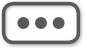

外耳道异物种类可分为动物性(如各类昆虫或爬虫类,图5-1)、植物性(谷类、豆类等,图5-2)及非生物性(如棉花、塑料、玻璃、纽扣电池、医用纱条等,图5-2)。Thompson等的一项回顾性研究揭示在162例外耳道异物中,棉花(22%)、昆虫(18%)和珠子(16%)是最常见的异物。异物可长时间滞留于外耳道,压迫周围组织,并可继发感染,最终导致局部组织炎症、坏死等,部分异物可被耵聍包绕形成耵聍栓塞。

图5-1 外耳道可见蚊子、蟑螂等小动物侵入